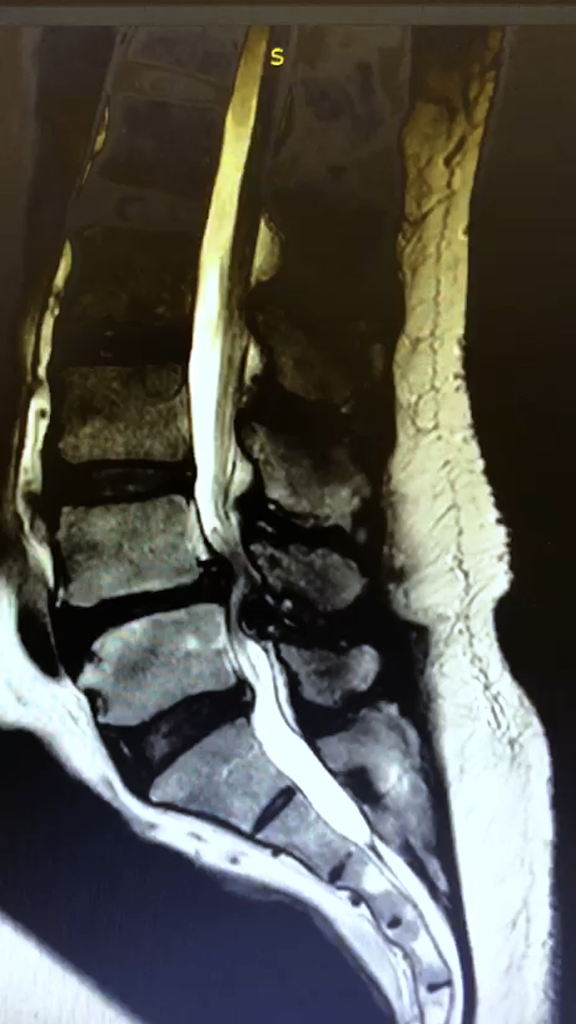

Na análise sagital é possível identificar o estreitamento marcado ao nível de L4–L5.

Imagem 1 – Corte sagital lombar (L4–L5)

Ressonância magnética evidenciando aperto significativo do canal lombar entre L4 e L5, com redução importante do espaço disponível para as estruturas nervosas.

No corte axial verifica-se um aperto completo do canal em L4–L5, restando apenas um pequeno espaço para a passagem dos nervos. No nível inferior, L5–S1, observa-se um prolapso discal. No entanto, o aperto crítico localiza-se em L4–L5. A hérnia projeta-se inferiormente e entra no forame, contribuindo para a compressão radicular.